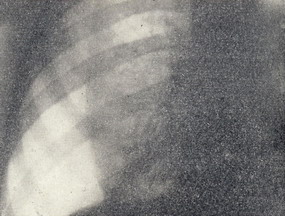

При поступлении состояние средней тяжести, имеется цианоз лица, пальцев рук. Наблюдается небольшая одышка в покое, усиливающаяся при движении. Больной правильного телосложения, пониженного питания - при росте 181 см вес 64 кг. Грудная клетка правильной конфигурации, при дыхании левая половина ее отстает. Число дыханий 22 в 1 минуту. Межреберные промежутки широкие. Перкуторно справа коробочный звук, слева звук с тимпаническим оттенком. Аускультативно справа дыхание прослушивается на всём протяжении лёгкого, жестковатое, слева дыхание не выслушивается. Голосовое дрожание слева отсутствует. Тоны сердца приглушены. Верхушечный толчок определяется у левого края грудины. Пульс 82 в 1 минуту. Артериальное давление 110/80 mm/Hg. Со стороны органов брюшной полости патологии не выявлено. Рентгенологически (рис. 1) левое легкое в состоянии коллапса. Вся левая плевральная полость заполнена газом. Средостение смещено вправо. На ЭКГ синусовая аритмия, вольтаж средний, электрическая ось сердца расположена вертикально. Диагноз: левосторонний спонтанный пневмоторакс.

Рисунок 1 – Прямая рентгенограмма грудной клетки больного А. при поступлении. Левое легкое поджато. Вся левая плевральная полость заполнена газом. Средостение смещено вправо.